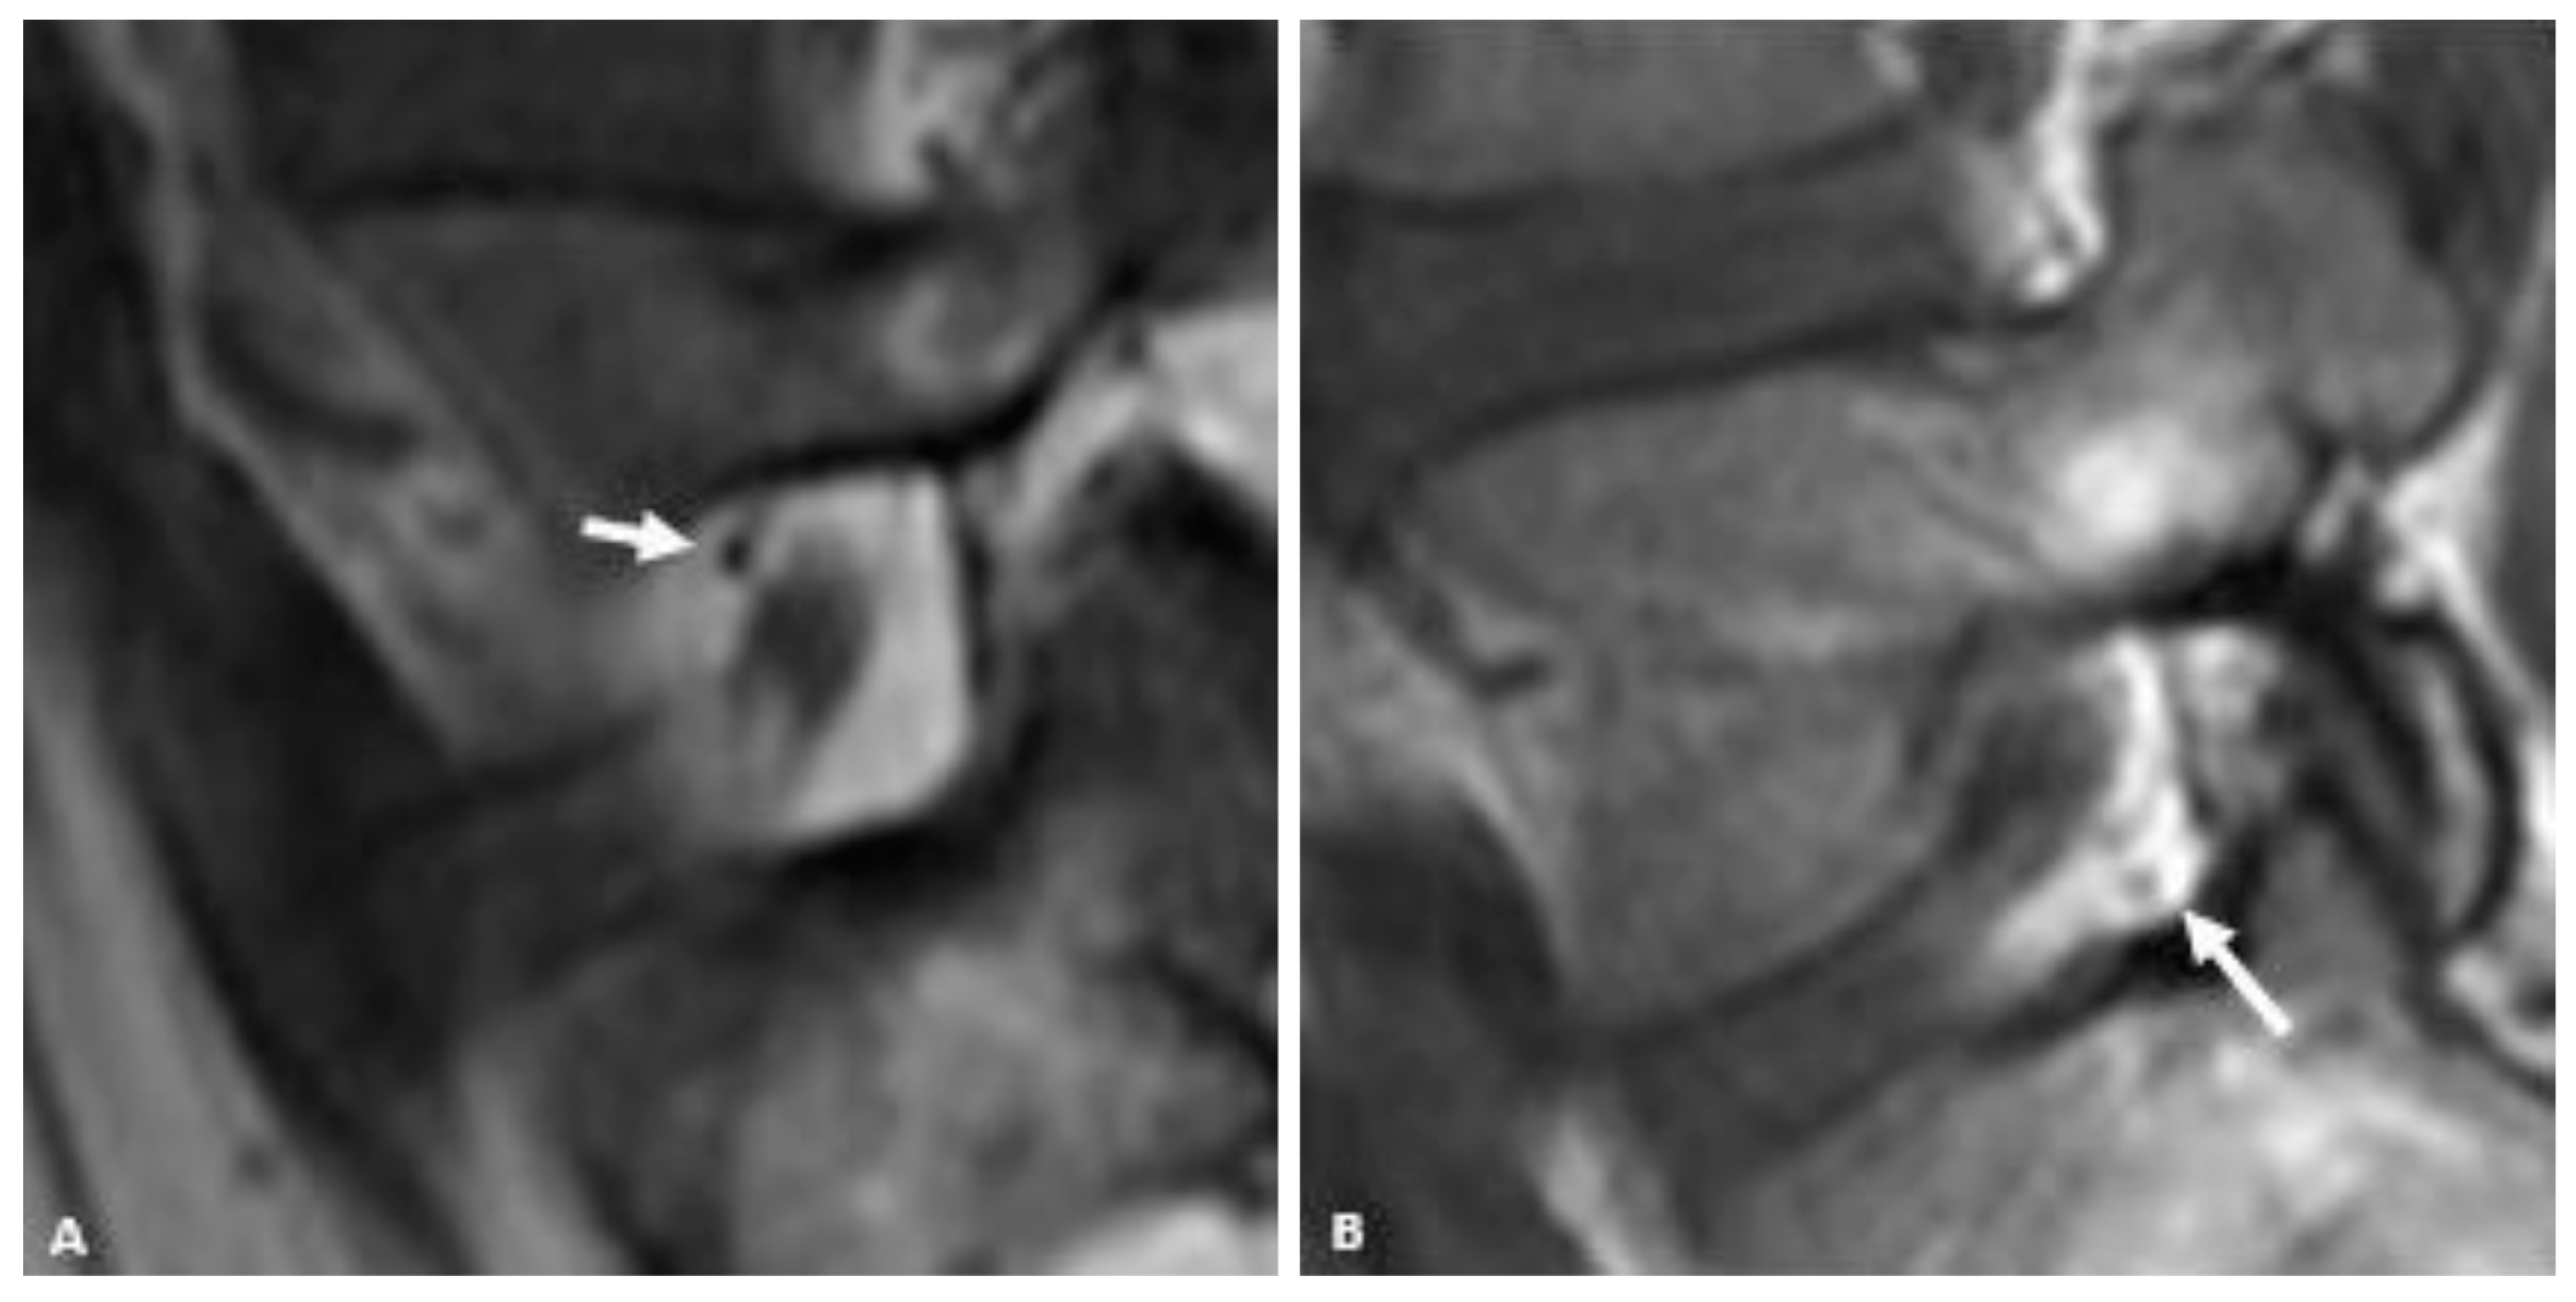

In this study, we demonstrated a difference in the distribution of foraminal fat in the postero-inferior and antero-superior foramen. In this population, 80% of L5-S1 foramina with moderate to severe stenosis had at least minimal postero-inferior epidural fat while just 40% of these same foramina had at least minimal fat in the antero-superior neural foramen. In fact, none of the foramina with moderate to severe stenosis had more than minimal foraminal fat in the antero-superior foramen. Even in patients without stenosis, more than 10% had no fat (“None”) in the antero-superior foramen, and only 31.6% had more than minimal fat in this location. Postero-inferiorly, all patients without foraminal stenosis had substantial foraminal fat. These findings for the L5-S1 foramen may support the notion that the postero-inferior approach (“Kambin’s triangle) for L5-S1 TFESI may be more advantageous than one in which the antero-superior foramen (“Safe triangle”) is targeted (Figure 3).

Figure 3.

59-year-old gentleman with L5 radiculopathy. (A) Sagittal T1w MR image demonstrates substantial fat in the postero-inferior foramen. The arrow corresponds to the needle trajectory for an infra-neural approach. Lateral (B) and frontal (C) fluoroscopic images during transforaminal epidural steroid injection show the needle projecting over the postero-inferior aspect of the foramen. The star is over the pedicle in (C). Contrast can be seen moving centrally towards the spinal canal within the inferior portion of the foramen.